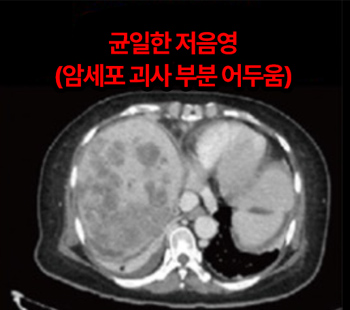

2023.2.2 腹部CT

2025.3.14 腹部CT

伴随肺转移的肝癌 4期 诊断

10日集中 高频热疗 实施